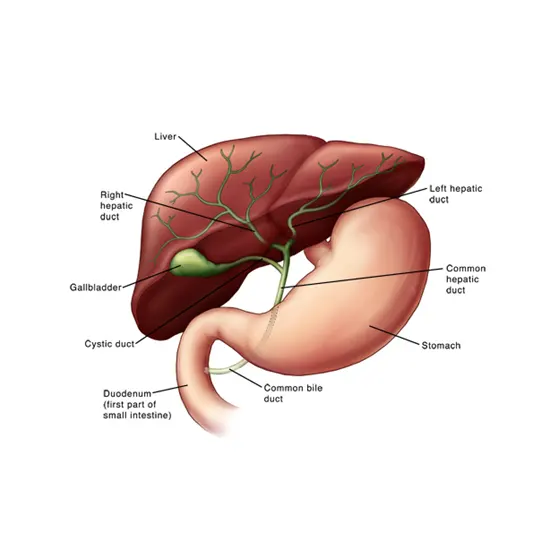

Gallbladder cancer is a type of cancer that originates in the gallbladder, a small organ located beneath the liver that stores bile, a digestive fluid. Gallbladder cancer is relatively rare, and it usually occurs in people...

Gallbladder cancer is a type of cancer that originates in the gallbladder, a small organ located beneath the liver that stores bile, a digestive fluid. Gallbladder cancer is relatively rare, and it usually occurs in people over the age of 65.